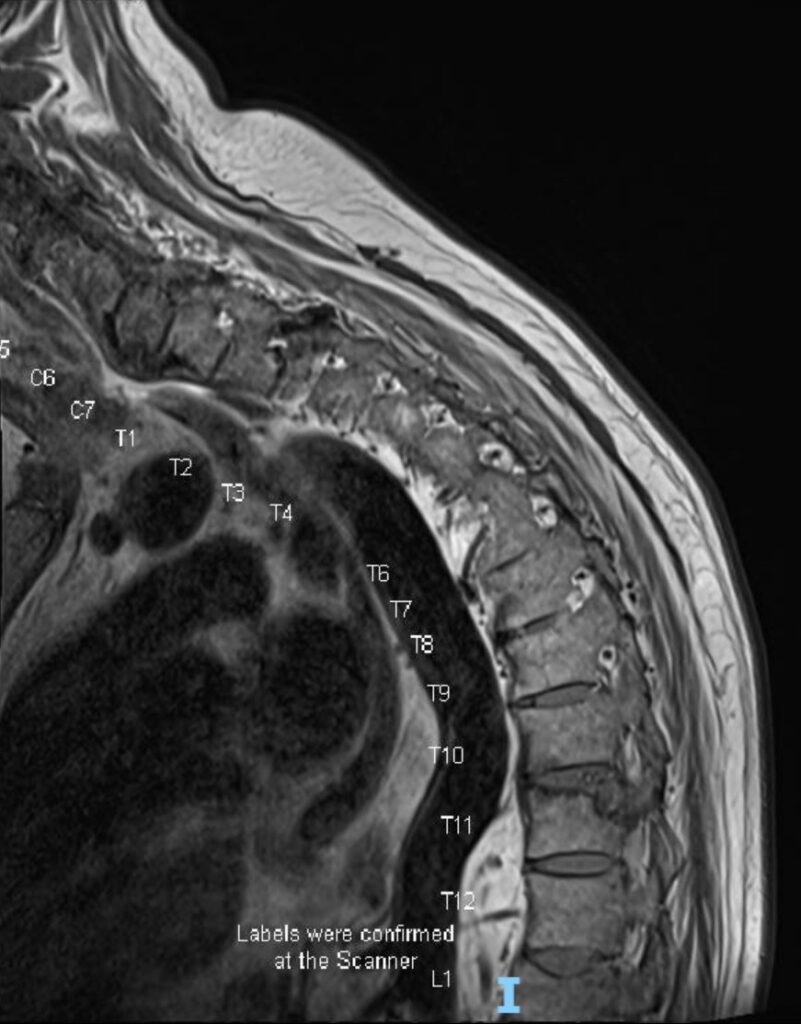

älterer Herr mit Rückenschmerzen. Diese bestehen seit langem, haben sich aber in letzter Zeit verschlechtert.

Oben: 3 Schichten der sagittalen T1 Sequenz

unten: 3 Schichten der sagittalen T2 mit Fettsättigung Sequenz

A. Warum hat der Patient schon lange Schmerzen?

B. Warum tut es in letzter Zeit vermehrt weh?